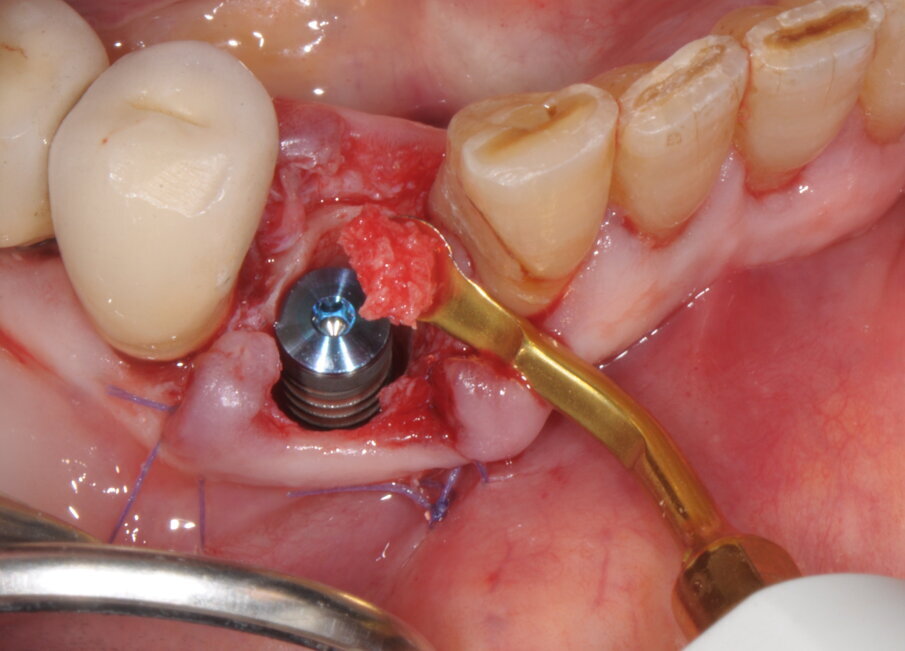

Dopo la verifica del corretto asse di inserimento e la valutazione del livello di profondità raggiunta rispetto ai picchi ossei dei denti vicini (mediante una replica), un impianto di 4 mm di diametro e 15 mm di lunghezza (BIOMET 3i BNST415) è stato inserito con un torque di inserimento >50Ncm (inizialmente con contrangolo chirurgico e successivamente manualmente). Immediatamente dopo è stata registrata, previo posizionamento di una diga di gomma a protezione dell’area chirurgica, la posizione dell’impianto attraverso un’impronta in silicone. Il difetto perimplantare è stato riempito con frustoli ossei recuperati attraverso una procedura di bone harvesting, con inserto OP3, da un piccolo accesso retromolare omolaterale e protetto mediante l’accollamento dei tessuti molli a un pilastro di guarigione di altezza 4 mm e dello stesso diametro implantare (Figg. 9, 10).

Fig. 9

Fig. 10